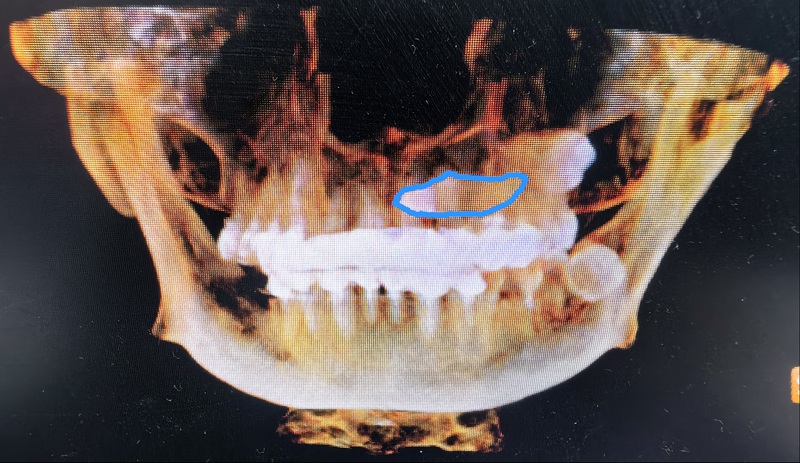

術前:尖牙橫行貫穿埋伏于左上頜骨內,牙冠位于上腭,牙根位于鼻根側下方。

劉弦醫生仔細查看口腔錐形束CT影像,發現這顆左上頜埋伏尖牙堪稱“定時炸彈”——碩大的牙根死死壓迫鄰牙,稍有拖延便會連累鄰牙不保。更棘手的是,這顆牙前臨鼻腔、后靠上頜竇,周圍纏繞著鼻腭神經血管束,拔除時稍有偏差,牙體就可能墜入鼻腔或上頜竇;面對謝女士“希望門診局麻下拔牙”的請求,這個手術難度堪比在精密儀器上“穿針引線”。